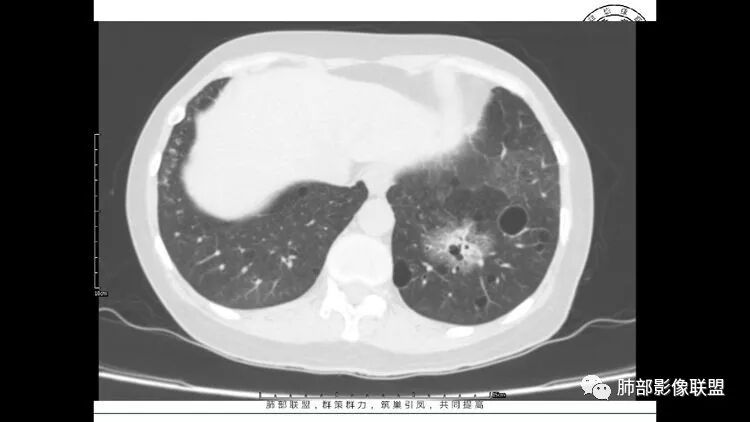

老年女性,眼炎入院,血常规正常,双肺多发囊状影,病变随机分布,形态单一,与血管关系密切,考虑LIP。左下肺混合GGO,边界尚清,贴近囊腔,鉴别腺癌。炎症指标无异常暂不考虑感染性病变。

胸CT:1.双肺多发囊性变,以中下肺为主,病变边缘可见肺动脉,部分囊内可见分隔及肺动脉,双下部分肺野周围可见小叶中心结节及树丫征。

2 左肺上叶尖后段 右肺上叶前段 右肺下叶外基底段 结节影,边界清楚,可见柔软毛刺,左肺下叶后基底段混合密度影。

3.纵隔淋巴结肿大?,以主动脉弓为界向上向下增大。

考虑:淋巴瘤肺浸润,眼部症状考虑与此有关;LIP?;继续鉴别肺腺癌?血管炎?。